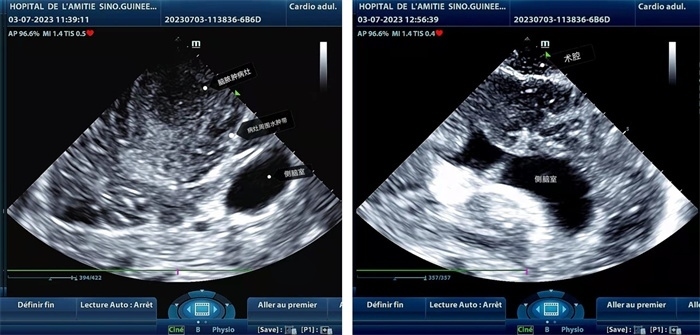

手術(shù)中,張國濱在超聲科顧秀娟的幫助下,運(yùn)用顱腦術(shù)中超聲技術(shù),通過將一次性保護(hù)套的超聲探頭置于腦組織表面,實時觀察病變的位置和形態(tài),進(jìn)一步確認(rèn)最佳手術(shù)路徑。術(shù)中超聲顯示,病變位于左額頂葉,大小約為4x4x3cm,邊界清晰,呈囊實性,周邊腦組織水腫明顯。最終,病灶順利切除,診斷為腦膿腫,并通過超聲檢測確認(rèn)術(shù)腔無病變殘留、無出血,為患者術(shù)后恢復(fù)提供了良好的保障。

左圖顯示術(shù)中超聲見囊實性病變,大小約為4x4x3cm,病灶周圍腦組織水腫明顯;右圖為病灶切除后,術(shù)中超聲示術(shù)腔無病變殘留

左圖顯示術(shù)中超聲見囊實性病變,大小約為4x4x3cm,病灶周圍腦組織水腫明顯;右圖為病灶切除后,術(shù)中超聲示術(shù)腔無病變殘留。中國第二十九批援幾內(nèi)亞醫(yī)療隊供圖